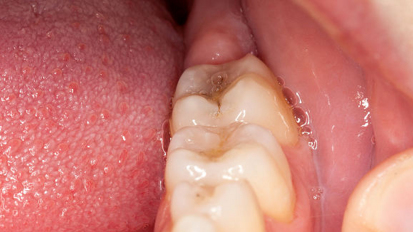

Zdravniki našli zobni implantat v nosni votlini

BRESCIA , Italija : Italijanski rinokirurgi so našli dislociran zobni implantat, ki je potoval navzgor skozi čeljustni sinus v etmoidne sinuse pri ...